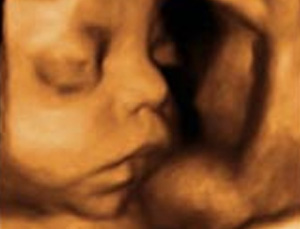

El bebé suele estar colocado de cabeza en la semana 31 de embarazo, pero aún hay tiempo para que se dé la vuelta varias veces. En la ecografía del tercer trimestre se puede valorar el crecimiento del pequeño, su grado de bienestar fetal, así como el estado de la placenta y del líquido amniótico. Tú tendrás que lidiar con las hemorroides y varices. ¿Cómo? Siguiendo una dieta rica en fibra, acompañada de ejercicio físico moderado.

Ecografía del tercer trimestre: qué busca

Entre las semanas 31 y 34 de embarazo es el momento de realizar la ecografía del tercer trimestre. Lo primero que se valora es la presencia de latido cardiaco y posteriormente la colocación de tu hijo: es la llamada presentación de cabeza o de nalgas. Pero lo más importante de esta ecografía es el estudio del crecimiento fetal mediante las medidas de la cabeza, el abdomen y el fémur -

Mediante la ecografía, se visualiza la localización de la placenta así como su grado de envejecimiento: existen cuatro grados de envejecimiento placentario a lo largo del embarazo. En esta semana del embarazo, lo normal es que la placenta tenga un grado 2-3 o 3. También se cuantifica la cantidad de líquido amniótico: lo que hacemos es medir los cuatro cuadrantes del útero y sumando entre todos más de 5 centímetros.